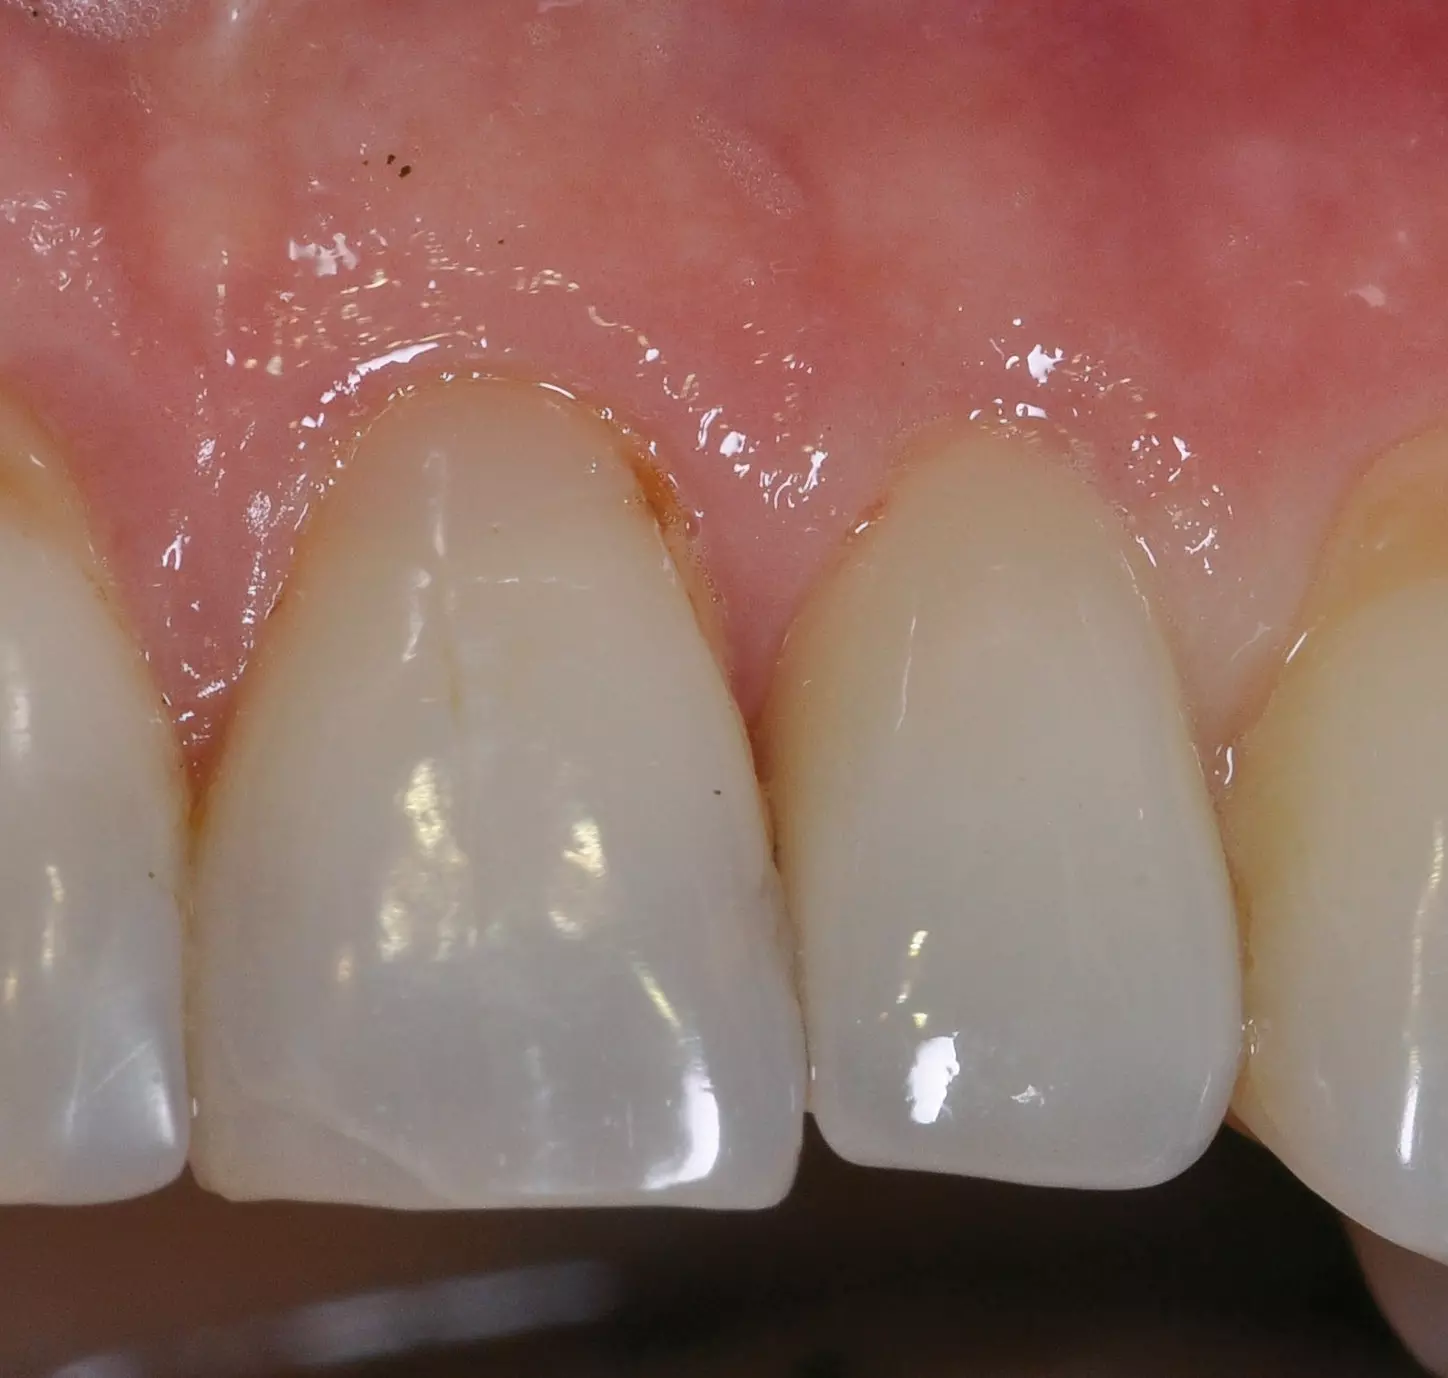

Präklinische und klinische Untersuchungen zu parodontologischen Parametern um „gesunde“ Titan- und Zirkonimplantate zeigen in Bezug auf die Sulcustiefen statistisch signifikante Unterschiede [36,37]. Die Werte erweisen sich sowohl im Tiermodell als auch beim Patienten höher bei den Titanimplantaten im Vergleich zu den Zirkonoxidimplantaten. Erfahrungsgemäß ist eine Sulcus-Sondierung am Zirkonoxidimplantat allerdings aufgrund der dichten fibrösen Gewebestruktur erschwert (Abb. 3).

Dr. Jacobi-Gresser

Augenscheinlich sind die ästhetischen Vorteile des Zirkonoxid-Implantatwerkstoffes im Vergleich zum Titan insbesondere in der anterioren ästhetischen Zone bei Patienten mit dünner Gingiva unter 2 mm [47] (Abb. 5–8).